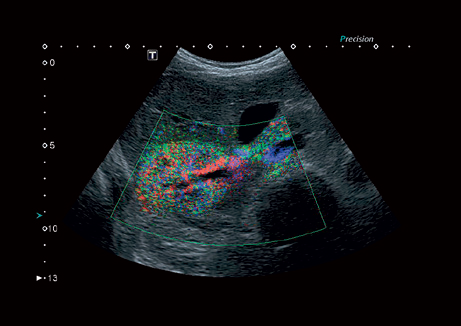

Режимы визуализации Canon (Toshiba) Aplio 300

B, M, PWD, CWD, ЦДК, THI, 4D, динамический поток (Dynamic Flow), энергетический доплер (Power), контрастная эхография (CHI 2D) и комбинированные режимы, включая следующие: B/M, B/PWD, BDF/PDW, BDF/MDF,BDF/MDF/PWD, 2D/CWD, BDF/CWD (BDF-режим изображения, в котором CFM изображение накладывается на B-режим изображения, MDF-режим изображения, в котором CFM изображение накладывается на M-режим изображения)

Энергетический допплер:

Да

Цветовой допплер:

• VRI - распознавание кровотока и тканевой перфузии

• Контрастная эхография;